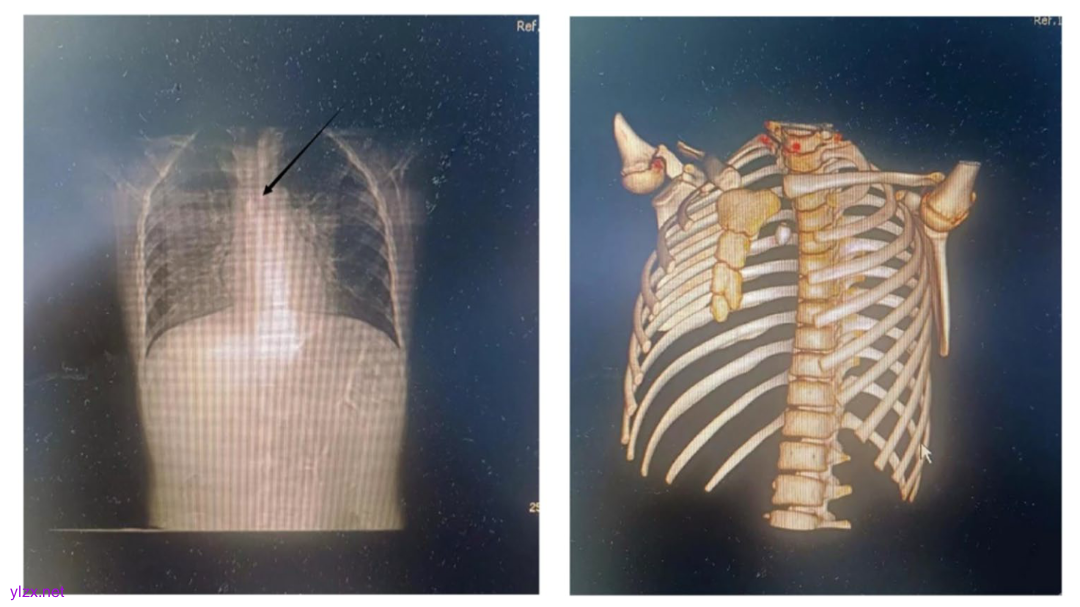

患儿,女,8岁,意外吸入异物14h后转诊至我院,临床表现为间歇性咳嗽、胸痛、喘息、恶心和呕吐。患儿既往体健,无特殊病史。转入急诊科时意识清醒、对答切题,生命体征平稳,血压100/52 mmHg,呼吸频率25次/分,心率100次/分。体格检查示双肺听诊呼吸音粗,可闻及喘息音和痰鸣音。胸部CT三维重建显示隆突稍上方高密度影,提示异物(图1)。支气管镜检查发现隆突上方一红色珠子样异物(约1.3 cm×1.5 cm),中央孔完全堵塞右主支气管开口,周围附着痰液,导致通气不良(图2)。

图1 8岁女孩气管内异物

A. 颈部 CT 轴位图像显示气管中线处异物(箭头所示)。B. CT 三维重建显示气管管腔内高密度异物影,位于隆突(主支气管分叉处)稍上方。